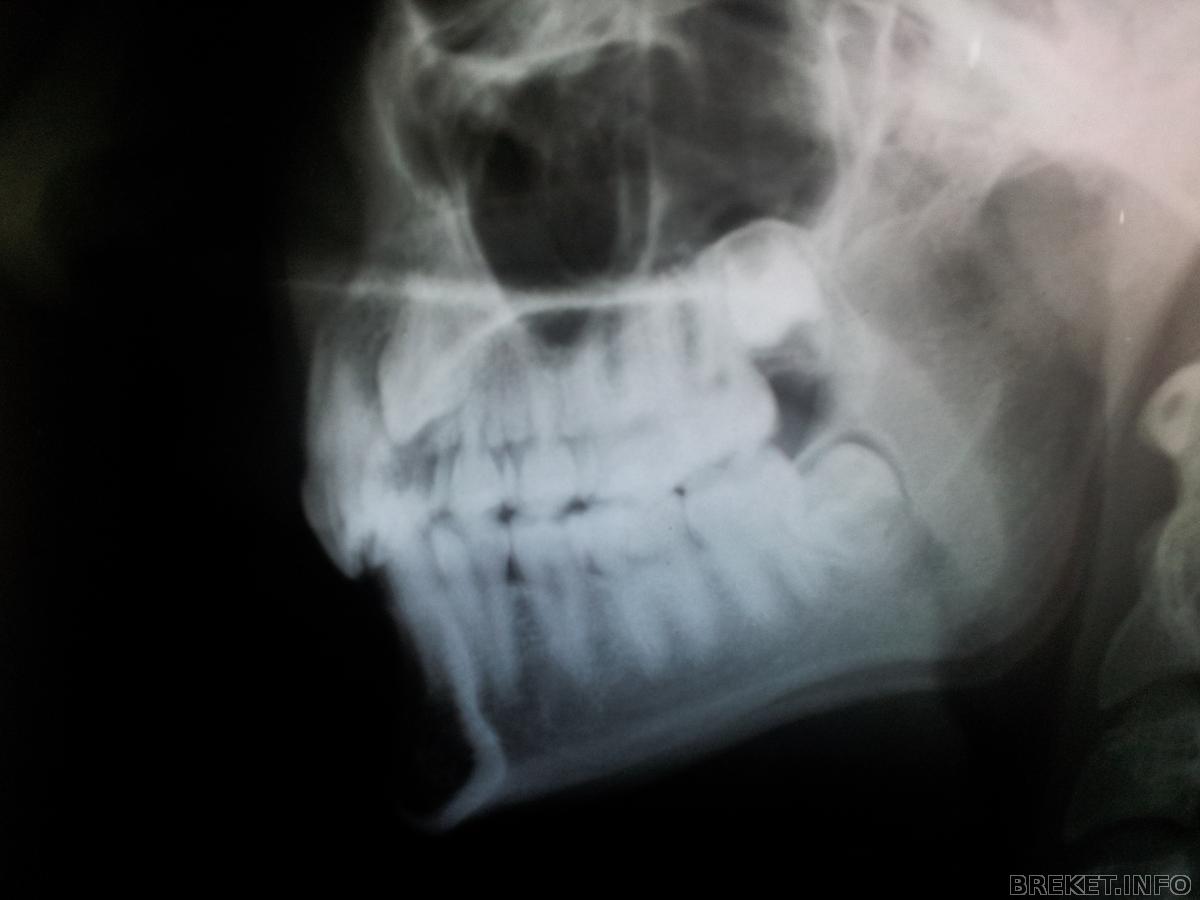

Снимки моего клыка.

Да, лежит он очень высоко, но зато хорошо лежит)